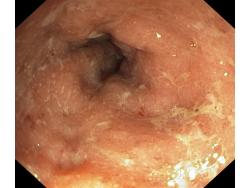

Zapalenie wrzodziejące jelita grubego